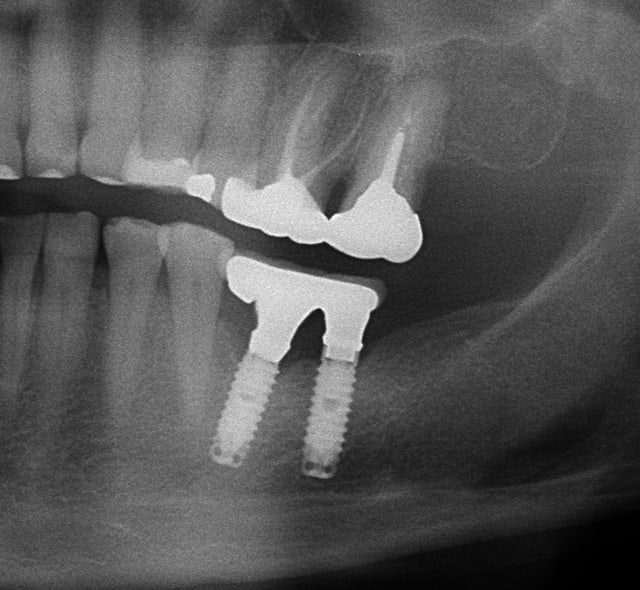

patiente

1)édentée bilaterale

2)bruxoman(girl)

3)suite implantaire difficile...n'a pas fait le travail de l'autre coté (à l'époque je faisais confiance et j'avais accepté de monter la prothèse)

4)la supra structure s'est dévissée deux fois en 7 ans et à chaque fois je la prévenais...

posté en même temps que la radio

donc oui à toutes tes suggestions

A propos de ce cas dont tu a herite je crois .

Ne penses tu pas que la fracture du ciol est lie aux tensions qui s'exerce contenu de l'inclinaison de l'implant et de l'extension mesiale